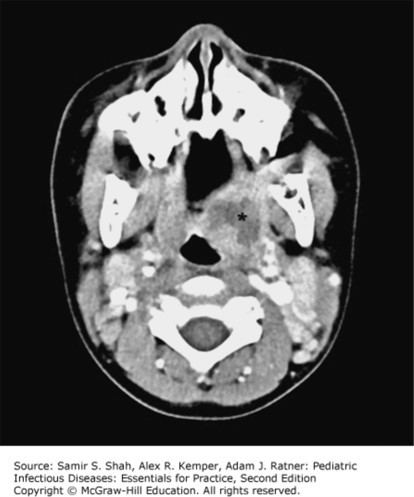

The correct answer is “C.” Classic physical exam findings for a peritonsillar abscess include severe sore throat, unilateral tonsillar swelling, trismus, and deviation of the uvula away from the affected side. Patients may also present with fever, drooling, odynophagia, and a muffled or “hot potato” voice. Hot potato voice is a buzz word for this infection. It is usually seen in older children and adolescents after an antecedent infection such as tonsillitis (option “E”), strep throat (option “D”) or a viral URI (option “A”). The physical exam is not consistent with sinusitis (option “B”).

Photo: Shah SS, Kemper AR, Ratner AJ. Pediatric Infectious Diseases: Essentials for Practice, 2e; 2019.